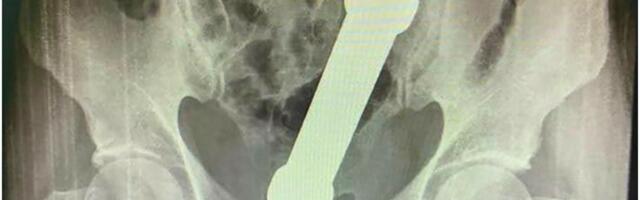

448 ŽALIO SE NA BOLOVE Lekari zanemeli kad su videli rendgenski snimak: Iz rektuma mu izvađen teg od 2 kilograma!

ŽALIO SE NA BOLOVE Lekari zanemeli kad su videli rendgenski snimak: Iz rektuma mu izvađen teg od 2 kilograma!

Šokantan slučaj je zabeležen u Brazilu.